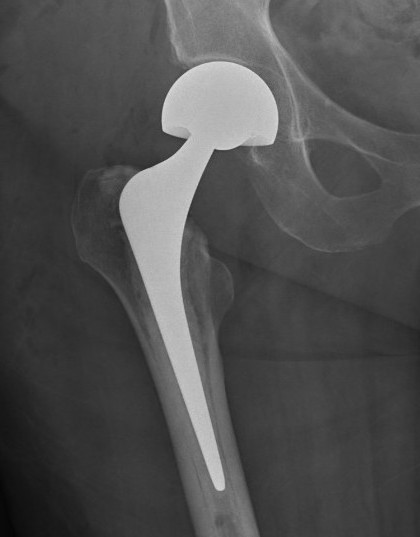

Total hip arthroplasty

Indications

Young, active, mobile patient with neck of femur fracture

Issues

THA

- better functional outcome in young mobile patient

- higher cost

- higher dislocation rates

Results

HEALTH investigators NEJM 2019

- RCT of 1495 patients > 50 with displaced femoral neck fracture

- HA versus THA

- reoperation rate same in both groups (8%)

- dislocation: 2% HA versus 5% THA

- serious adverse events: 37% HA verus 42% THA

- modest improvement in function for THA over HA, clinically unimportant